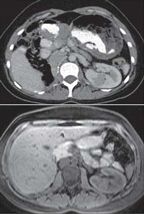

Central posterior medial lesion in the midportion of the left kidney revealed by axial–post-contrast CT (top) and T1 pre-Vibe fat sat MRI (bottom)